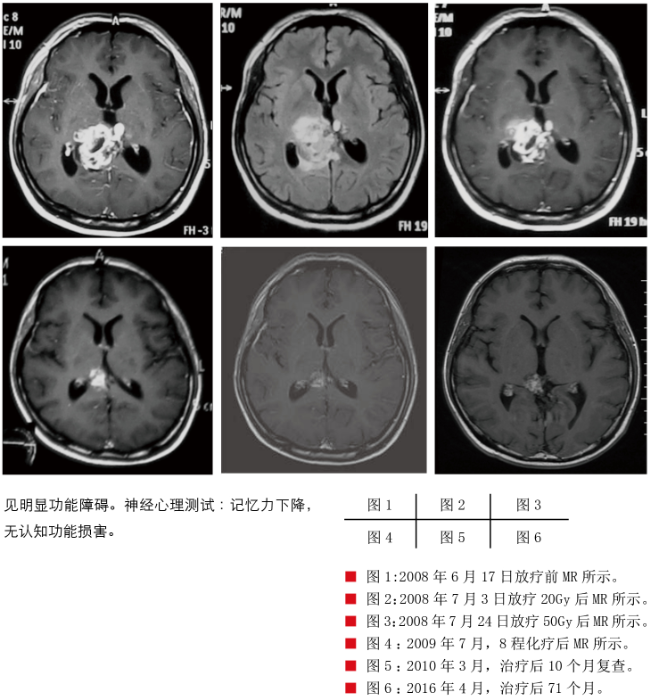

患者赵某某,男,21岁,因“反复头晕、视力下降1月余”于2008年6月16日首次入院。既往史无特殊。入院查体:神志清楚,颈无抵抗。双侧瞳孔等大等圆,对光反射迟钝。视力右眼5.1,左眼4.8;双侧视乳头轻度水肿,双侧病理征(+),闭目难立征(±)。影像检查:头颅CT及MR:

2、梗阻性脑积水。全脊髓MR未见明显异常。实验室检查:血清:HCG 39.2mIU/ml(<30) ,AFP 952ng/ml(0.6-7);脑脊液: HCG 36mIU/ml(<30), AFP 174ng/ml(0.6-7)。根据患者症状、体征、影像学及实验室检查结果,临床诊断为:松果体区非生殖性生殖细胞瘤。于2008年6月20日开始行病灶局部三维适形诊断性放疗DT 20Gy/10F,完成后复查MR示病灶明显缩小。于2008年7月4日开始行全中枢放疗DT 30Gy/15F,病灶进一步缩小,于2008年7月25日行残留病灶X刀治疗DT 10Gy/1F。于2008年8月26日至2009年5月12日行BEP方案辅助化疗8程。治疗后患者头晕逐渐缓解,视力较前明显改善,肿瘤标记物下降至正常。2016年4月1日返院复查,患者无不适主诉,查体:神志清楚,颈无抵抗。双侧瞳孔等大等圆,对光反射灵敏。视力右眼5.2,左眼5.1。共济失调(-),病理征未引出。影像检查:头颅及全脊髓MR未见肿瘤复发征象。实验室检查:血清及脑脊液肿瘤标记物无异常。康复评估:未见明显功能障碍。神经心理测试:记忆力下降,无认知功能损害。